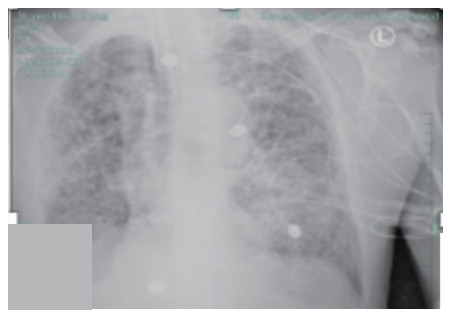

1 病例资料病例1:患者,女性,14岁,因“气急2 h”于2019-6-29入院。患者于2019年6月29日在杭州某医院行全麻下妇科手术,手术过程顺利,术中补液1 L(100 min输注500 mL胶体液+500 mL晶体液)。术后患者苏醒拔除气管插管,术后返回病房。拔管后0.5 h患者突发持续2 min的喉鸣和呃逆,之后迅速出现胸闷气急,血氧饱和度进行性下降到72%,伴有咯大量粉红色泡沫痰。立即予以高流量吸氧、速尿20 mg静注、西地兰0.2 mg静注治疗,8 min后症状略有所好转,血氧饱和度上升到97%,立即转送本院。体格检查:体温36.2℃,血压101/57 mmHg(1 mmHg=0.013 kPa),脉搏120次/min,呼吸22次/min。口唇不发绀,右肺叩诊浊音,双肺呼吸音粗,右下呼吸音低,右肺闻及较多细湿啰音;心率120次/min,律齐,无杂音;下肢无水肿。血白细胞4.7×109/L,中性粒细胞86.9%,血红蛋白155 g/L,C反应蛋白1 mg/L;N端脑钠肽前体(NT-proBNP)255 pg/mL;血浆乳酸5.4 mmol/L;生化:白蛋白34.7 g/L, 球蛋白19.3 g/L,余正常。胸部CT显示两肺大片渗出及实变影,以右肺为主,伴有右上叶小叶间隔增厚(见图 1)。入院诊断:负压性肺水肿。入院后予以速尿20 mg静注一次和甲基强的松龙40 mg静注一次,同时高流量吸氧,患者术后第2天后症状明显改善,术后第3天完全消失,术后第4天复查肺部CT病灶完全吸收(见图 2)。

| 图 1 病例1术后当天胸部CT |